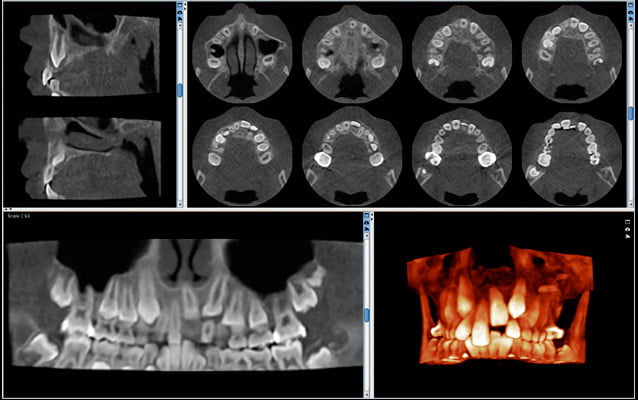

Optymalna równowaga między jakością i dawką

W pełni innowacyjny i naukowo zatwierdzony protokół obrazowania oparty na inteligentnych algorytmach 3D znacznie zmniejsza dawkę dla pacjenta bez pogorszenia jakości obrazu, zapewniając klinicystom na całym świecie możliwość skutecznego stosowania ALADY (minimalnej akceptowalnej diagnozy). Dążymy do tego, aby mieli taką możliwość. Stosowanie i skuteczność Donk Eye zostało naukowo zbadane i udowodnione w różnych badaniach.

Rozdzielczość dla niskiej dawki

wielkość woksela 400 μm, dawka pacjenta ~30 μSv

Mniejsza szczegółowość, niska dawka

Rozdzielczość dla niskiej dawki przy dawce ultraniskiej

wielkość woksela 400 μm, dawka pacjenta ~6 μSv

Mała szczegółowość, bardzo niska dawka